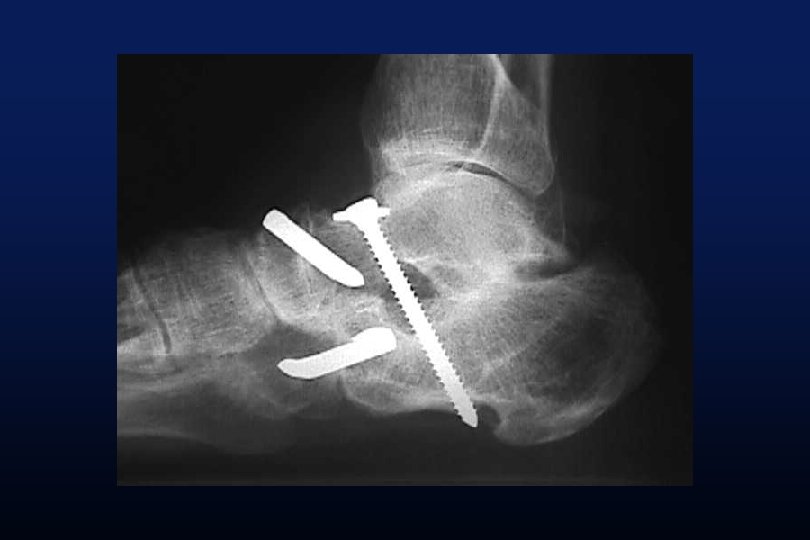

INTERVENTION DU CAVALIER

TRANSLATION MEDIALE ABAISSEMENT DE LA GROSSE TUBEROSITE DU CALCANEUS

Evans